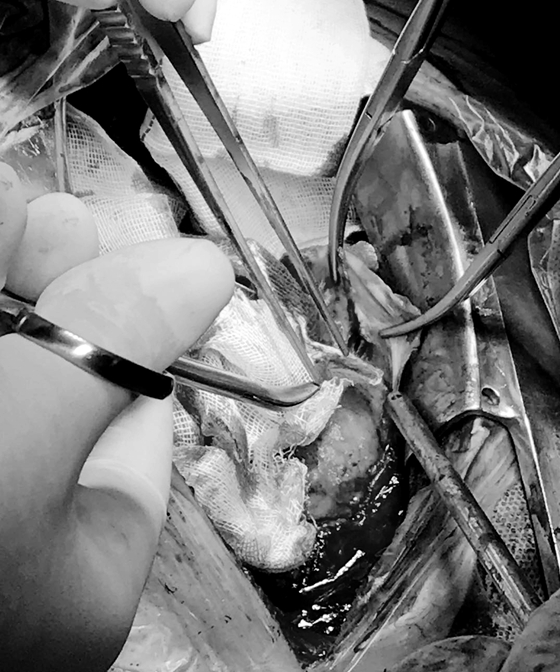

6月29日,手术如期进行,当黄教授团队打开患者胸腔时,看到心包纤维化,部分缩窄增厚,特别是上下腔静脉处,这无疑证明了黄日茂教授术前的诊断是正确的。术中予以剥除了增厚的心包,在剥除外面那层与心脏完全粘连的外衣时,还不能损伤心脏,手术必须特别小心,不然极容易造成大出血。

术中